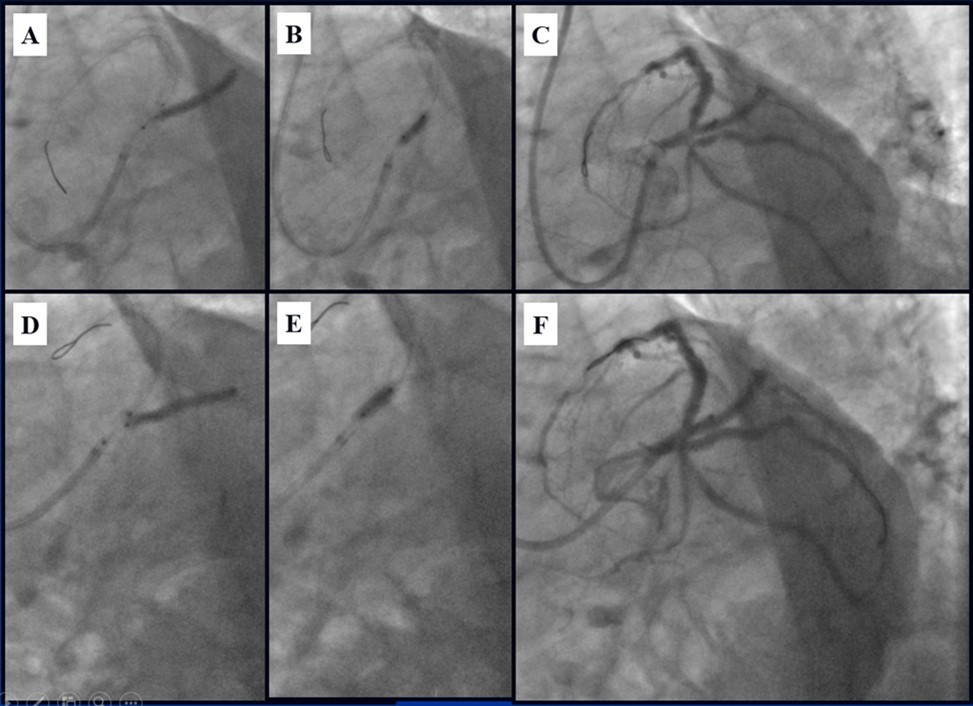

Angiography revealed rare anatomical variation LMCA quadrifurcation (Figure 1, Figure 2), 50% stenosis of the distal part of the LMCA, 40% stenosis of the ostial segment of left anterior descending (LAD) artery and diffuse prolonged 70-75-95% stenosis in mid-segment (Figure 3), 75% stenosis of the ostial segment of the circumflex (CX) artery, 75% stenosis of the ostial segment of the first marginal branch (OM1), 75-90% stenosis of the proximal segment of the intermediate artery (IMA), prolonged diffuse severe 90-95% stenosis of mid-segment of the right coronary artery (RCA) (Figure 4).

Figure 10.Stenting of the LMCA quadrifurcation: A, B - balloon modified mini crush stenting of the IMA, C - angiography result, D,E - modified balloon crush stenting of the CX-OM1, F - angiography result.

Figure 11.Stenting of the LMCA quadrifurcation: A, B – Stenting of the LMCA; C –Kissing balloon post dilatation of the IMA-LMCA-LAD; D - Kissing balloon post dilatation of the CX-OM1-LMCA; E, F - angiography result.